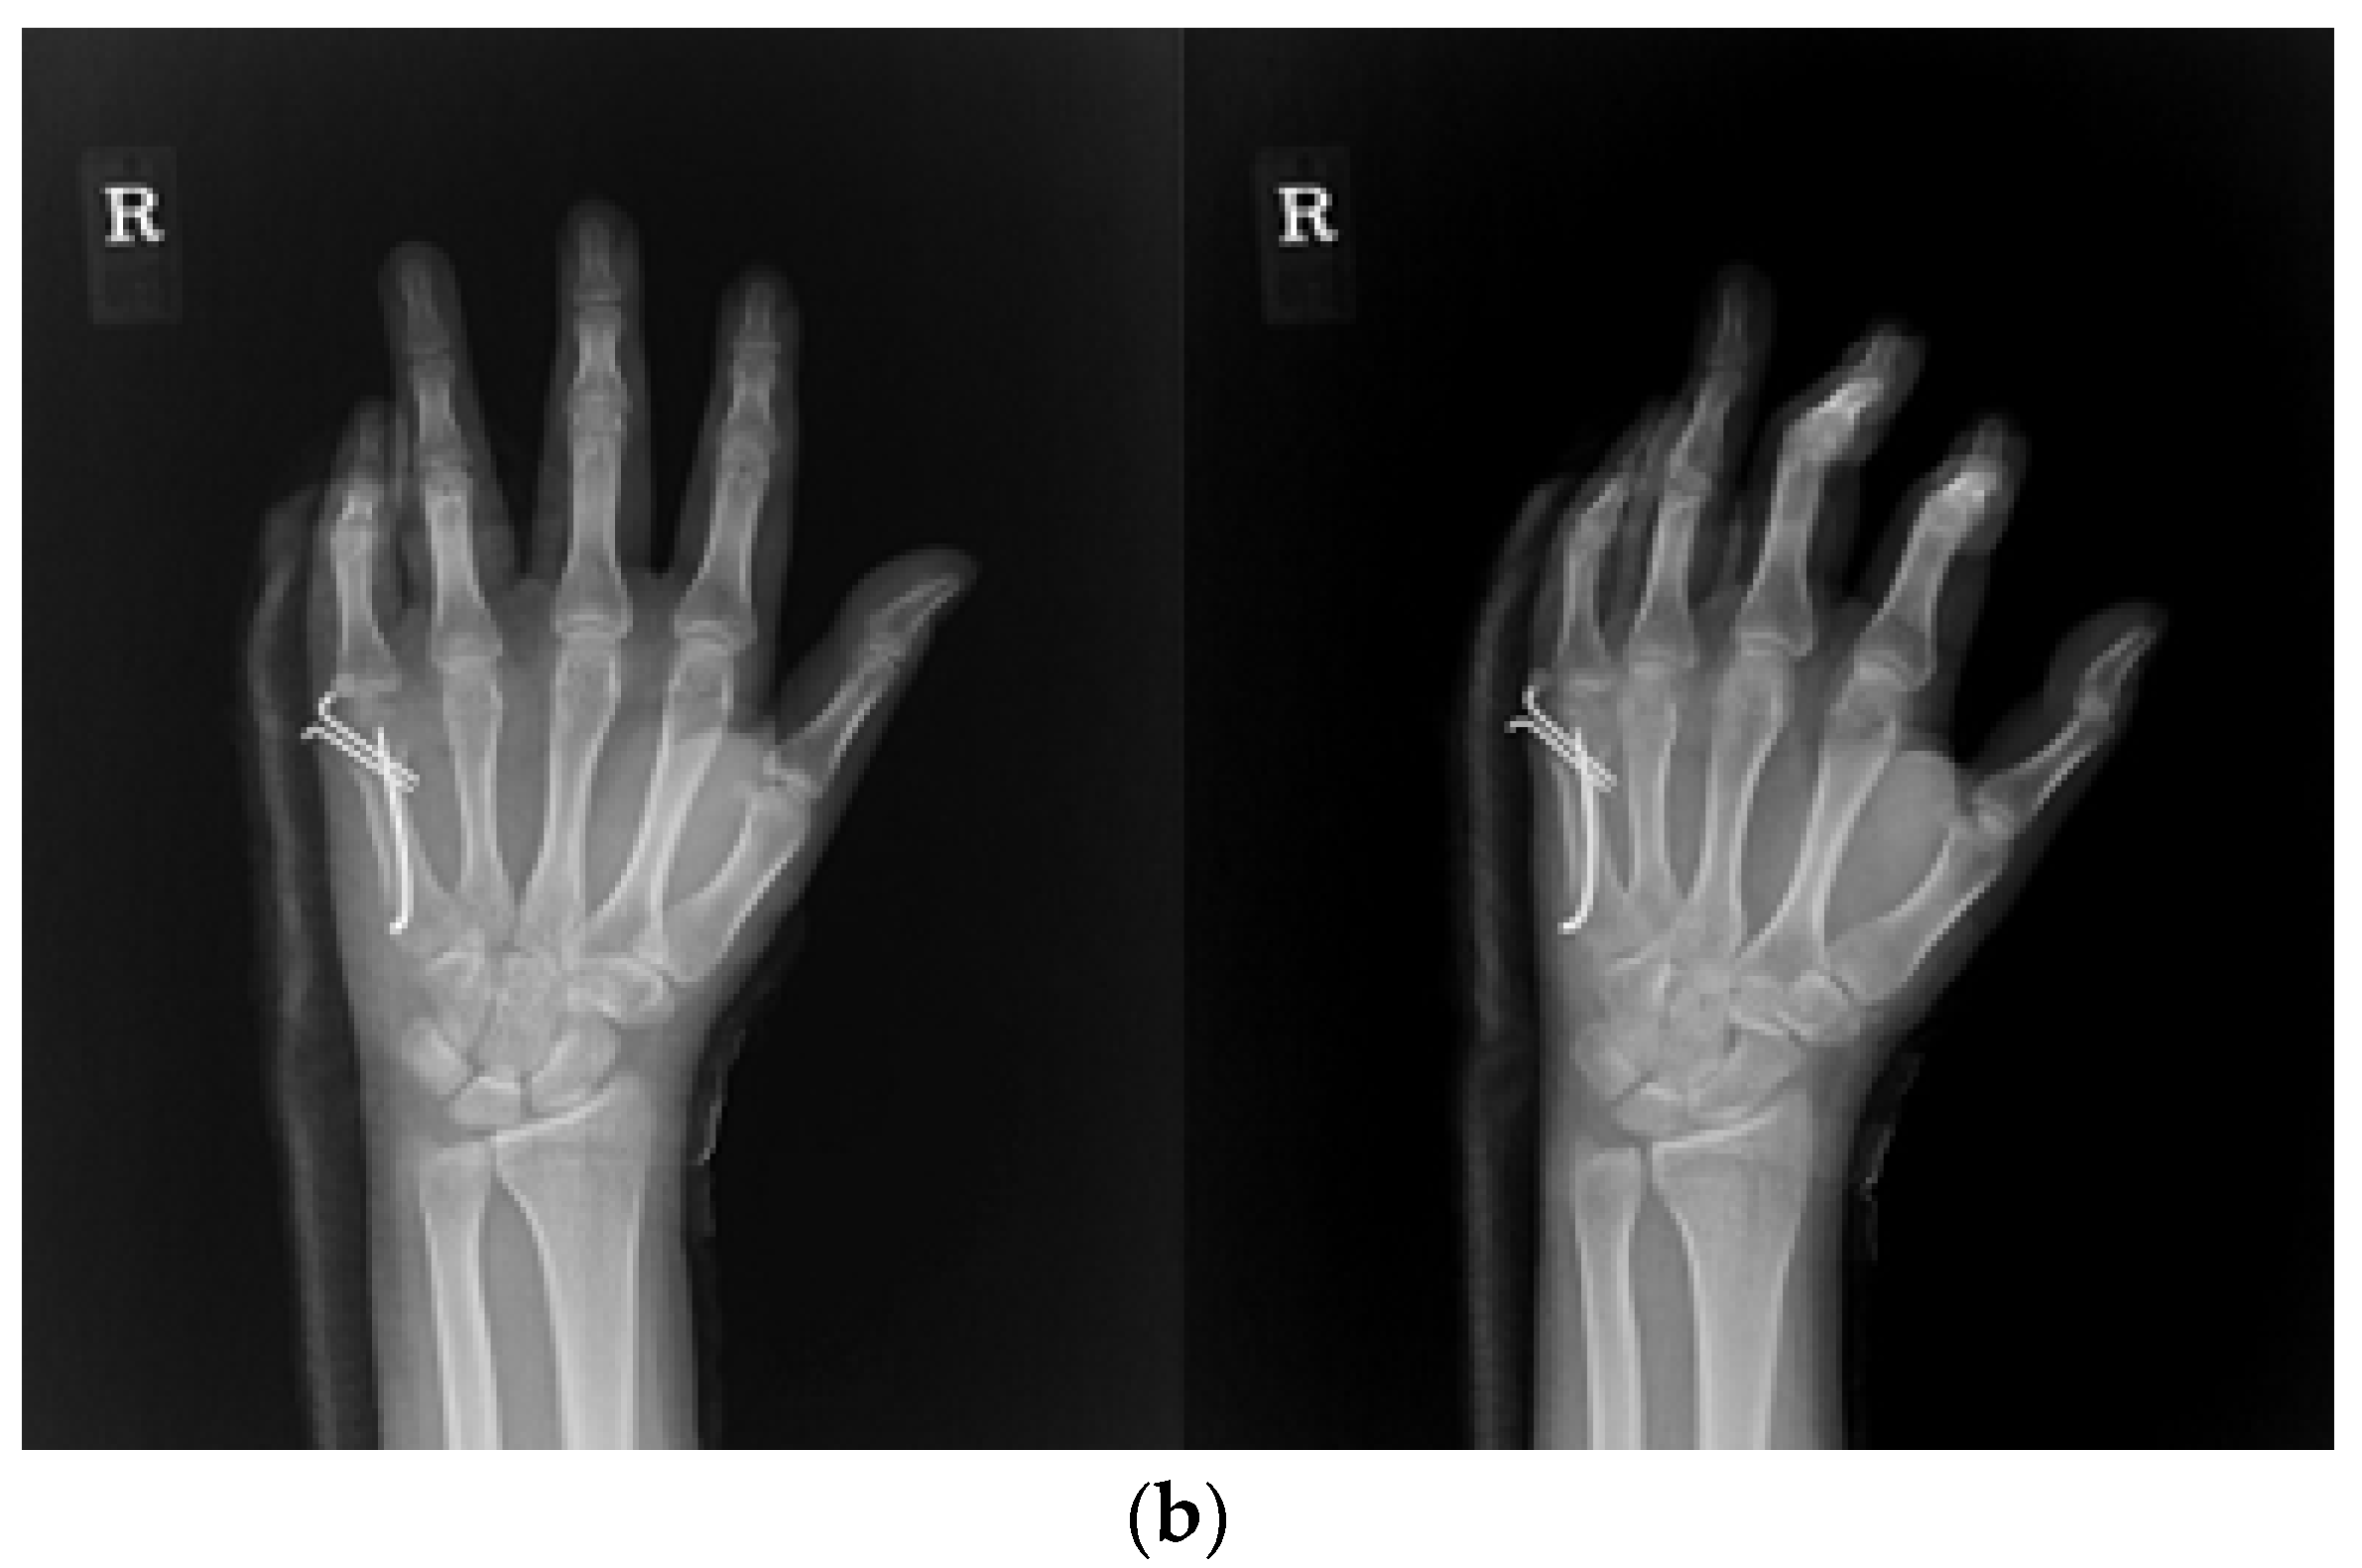

2.3. Surgical Technique